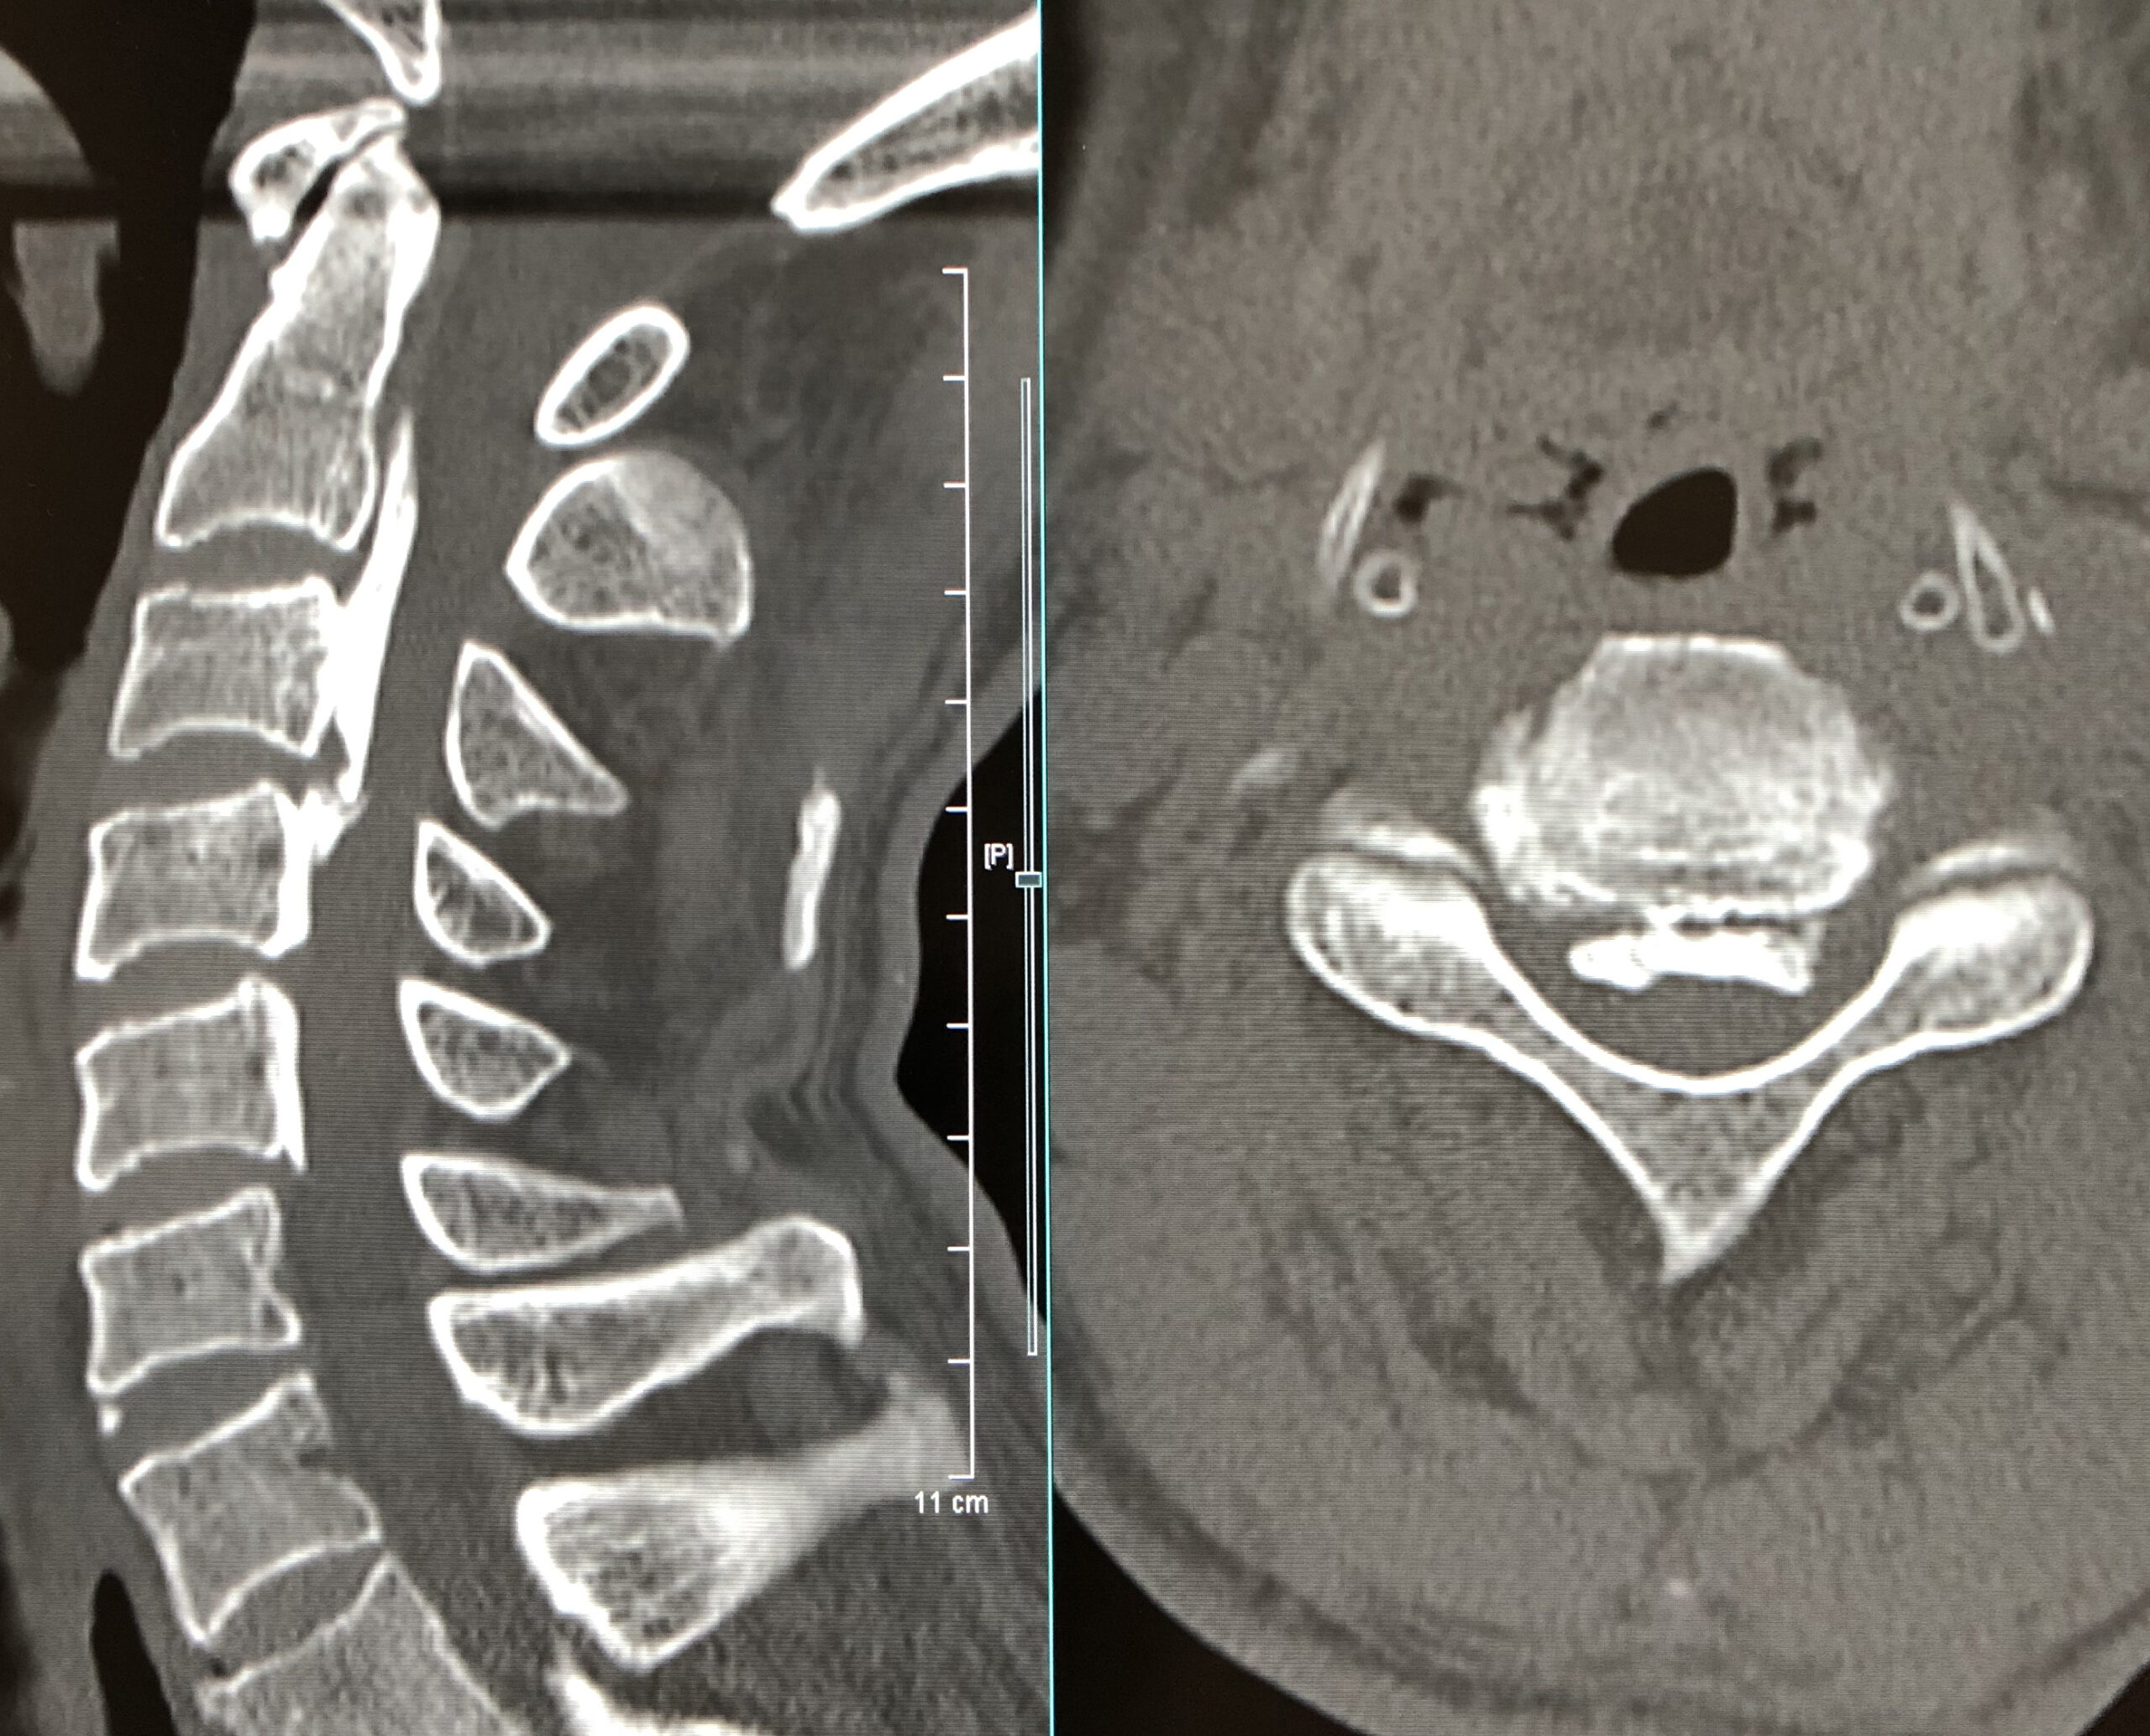

頚部脊柱管を後方から拡大し、脊髄の圧迫を除く手術方法です。

手術後は脊柱管が明らかに拡大しています。

| 術前 | 術後 |